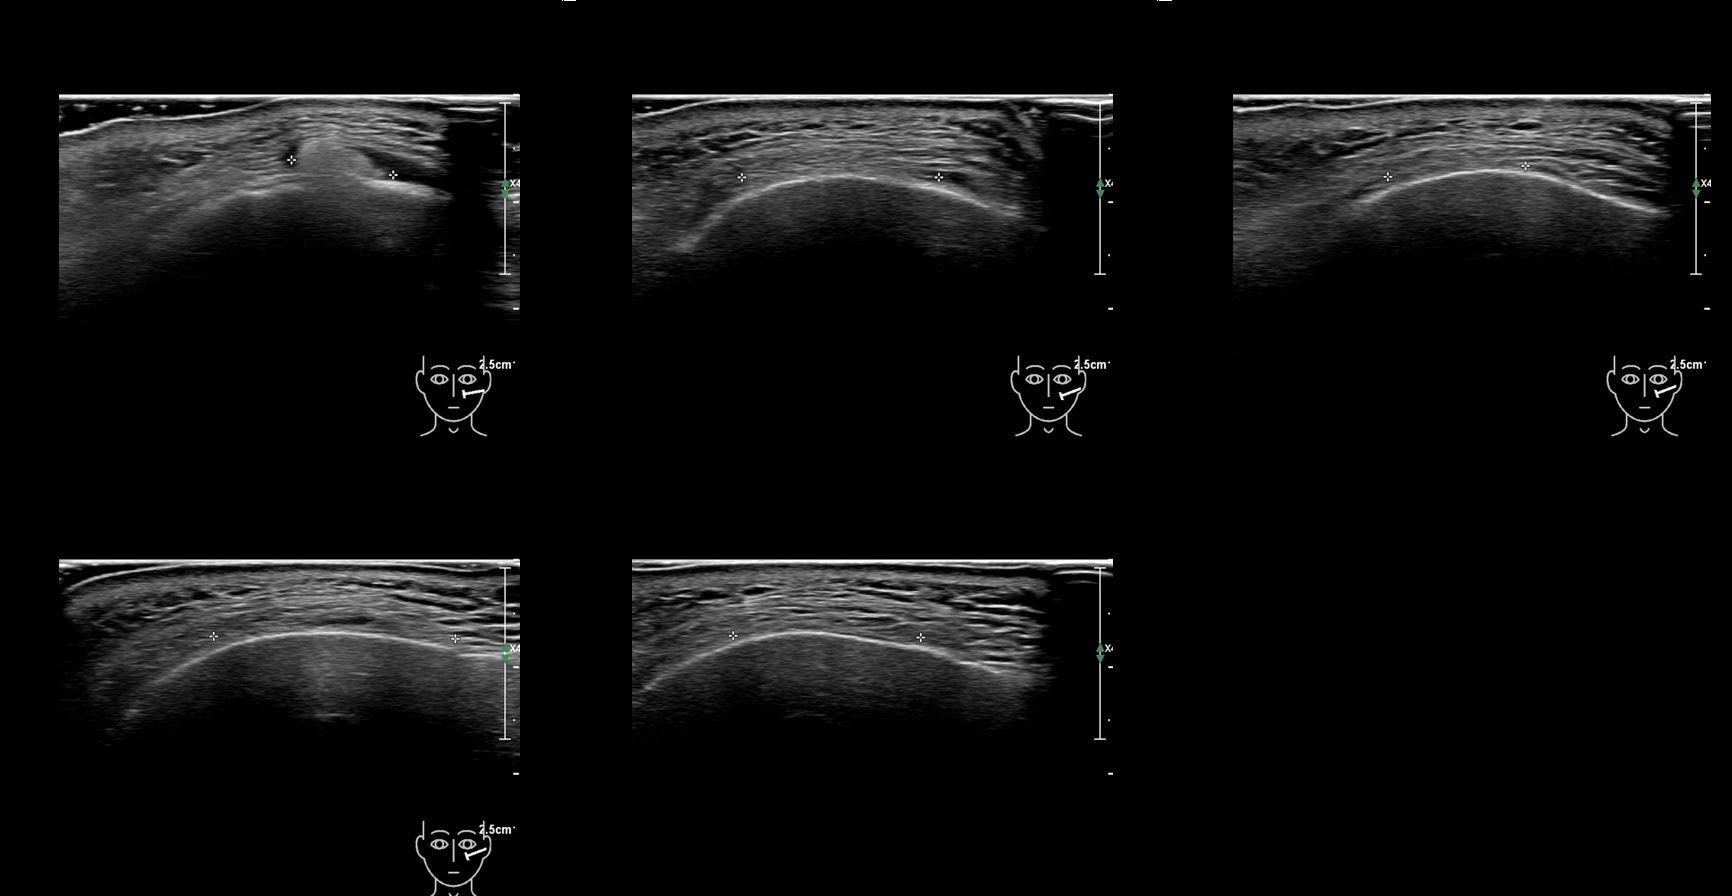

Fillers

Draw in the second image below where the fillers are located. To check if your answer is correct, swipe the first image to the right.